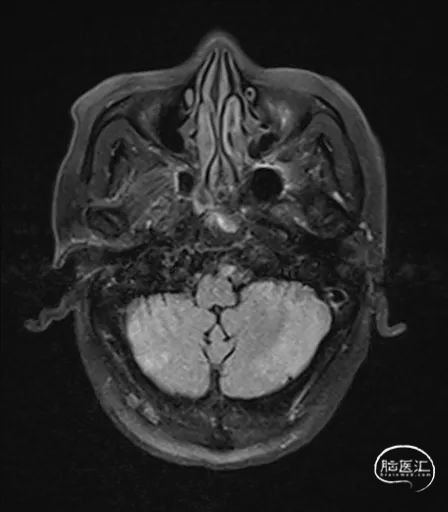

MRI提示小脑缺血性改变。

术后9天MRI:

术后CT:未见明显脑出血,双侧小脑低密度影。